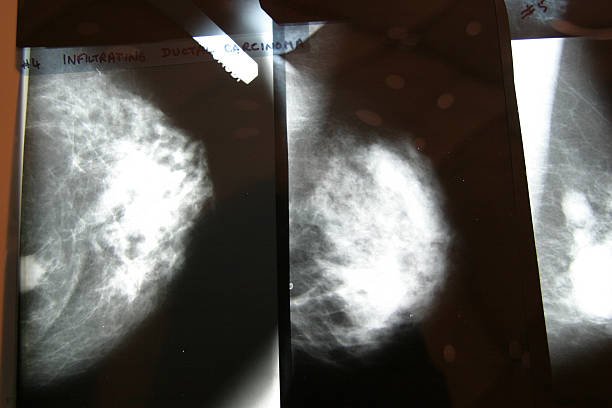

Il existe divers types de dépistage qui sont particulièrement pertinents pour les femmes. Parmi les plus courants figurent la mammographie, qui permet de détecter précocement le cancer du sein, ainsi que les tests Pap, qui sont cruciaux pour le dépistage du cancer du col de l’utérus. Également, d’autres évaluations telles que le dépistage de l’ostéoporose et des maladies cardiovasculaires peuvent s’avérer primordiaux. Ainsi, le dépistage précoce représente un pilier fondamental de la santé des femmes, garantissant leur capacité à vivre une vie saine et pleine d’énergie.

Le dépistage précoce constitue un outil essentiel dans la santé des femmes, notamment pour la détection de diverses maladies. Parmi les dépistages les plus recommandés, le dépistage du cancer du sein occupe une place centrale. Les femmes sont encouragées à commencer les mammographies à partir de l’âge de 40 ans, avec une fréquence de tous les deux ans jusqu’à 49 ans. À partir de 50 ans, une mammographie annuelle est souvent conseillée. Ce dépistage permet de détecter les anomalies dans le tissu mammaire à un stade précoce, alors que le traitement peut être plus efficace.